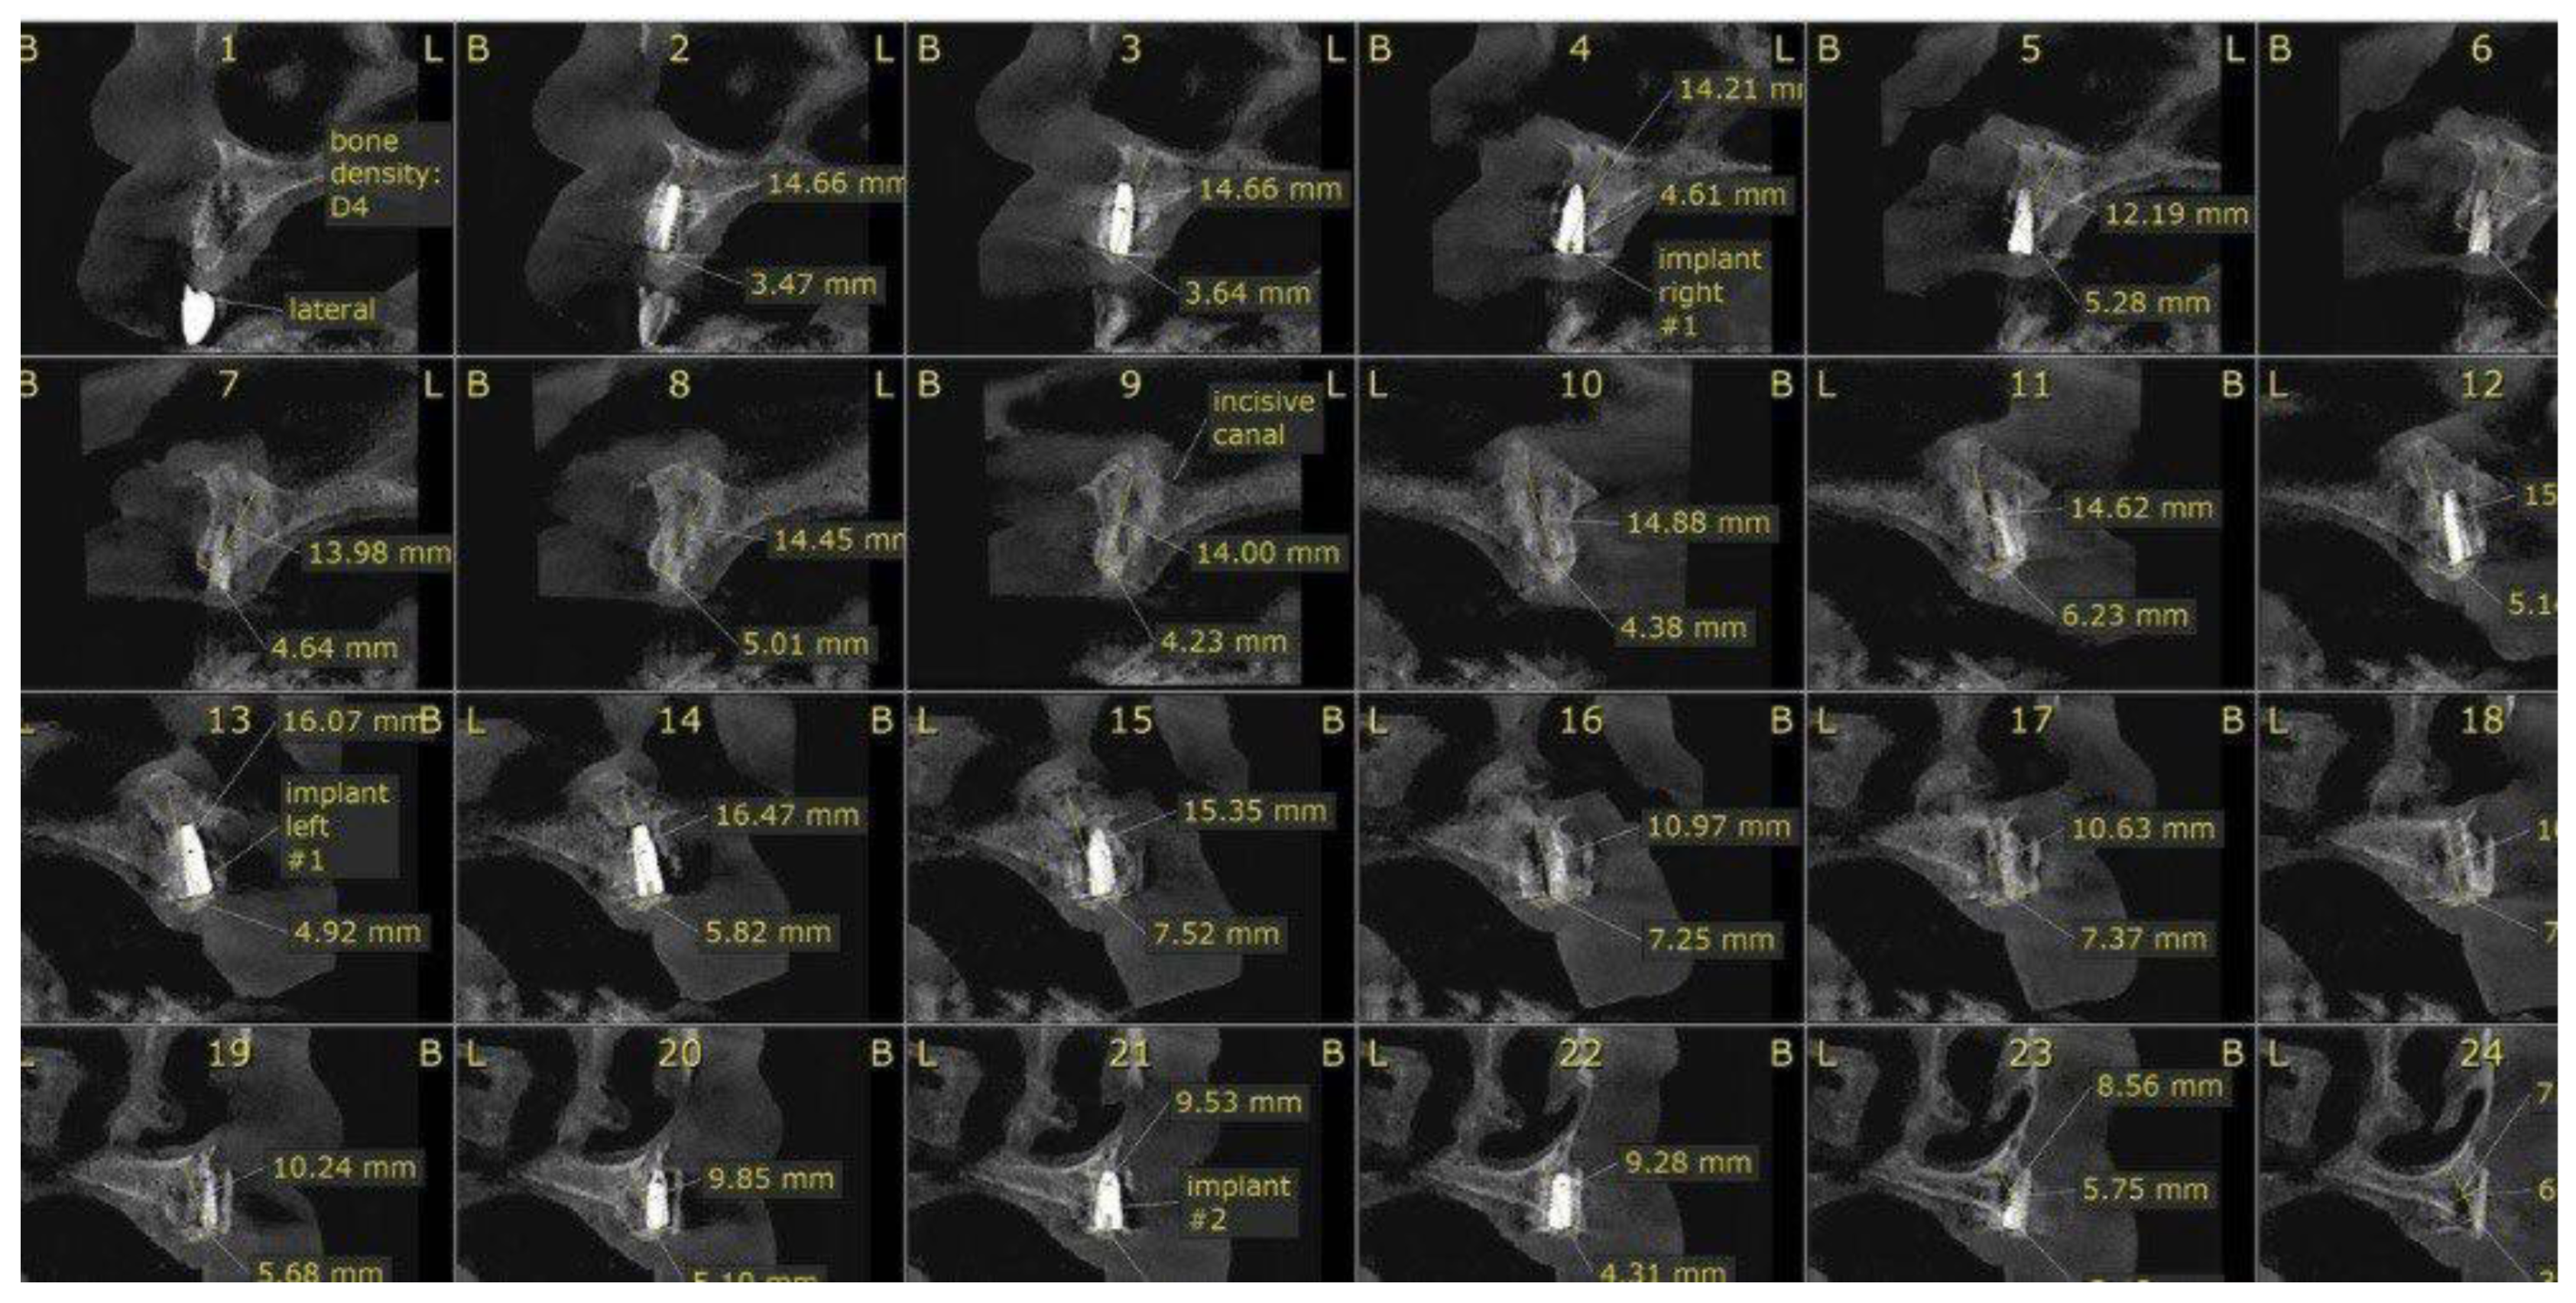

CBCT scans at follow-up confirmed stable bone levels and healthy peri-implant soft tissue with no measurable bone loss(Figure 9).

Figure 4. Preoperative CBCT scan (axial/cross-section) demonstrating minimal ridge width and height.

Preprints 172730 g003

Figure 5. Preoperative CBCT scan (axial/cross-section) demonstrating minimal ridge width and height.

Figure 9. CBCT scan taken six months after implant placement showing stable bone levels around all implants with no detectable bone loss (0 mm).